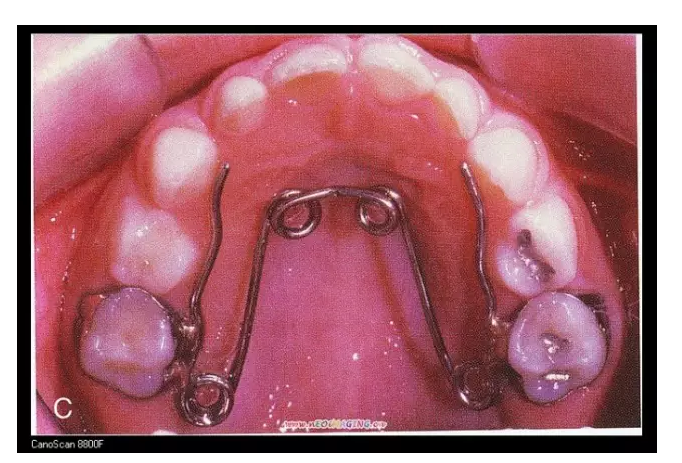

一、預(yù)防矯治器

在部分患兒5-8歲左右,由于乳牙反咬合或者牙弓過窄等情況,可能經(jīng)過評估,醫(yī)生會建議使用預(yù)防矯治器或片段弓來解決。